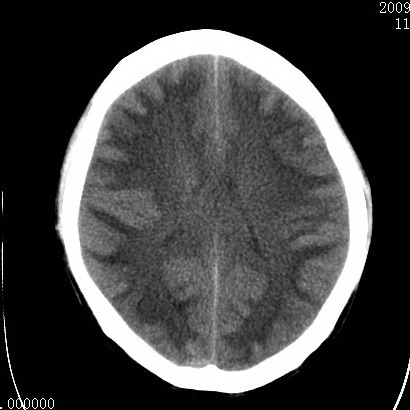

以下是引用余辉在2009-4-9 17:34:00的发言:[br]双侧脑白质对称性弥漫性密度减低,脑室脑沟裂池变小,双侧豆状核对称低密度,脑干对称性低密度,考虑1中毒性脑病2电解质异常(低钾钠等)3代谢异常及维缺乏等,进一步检查。